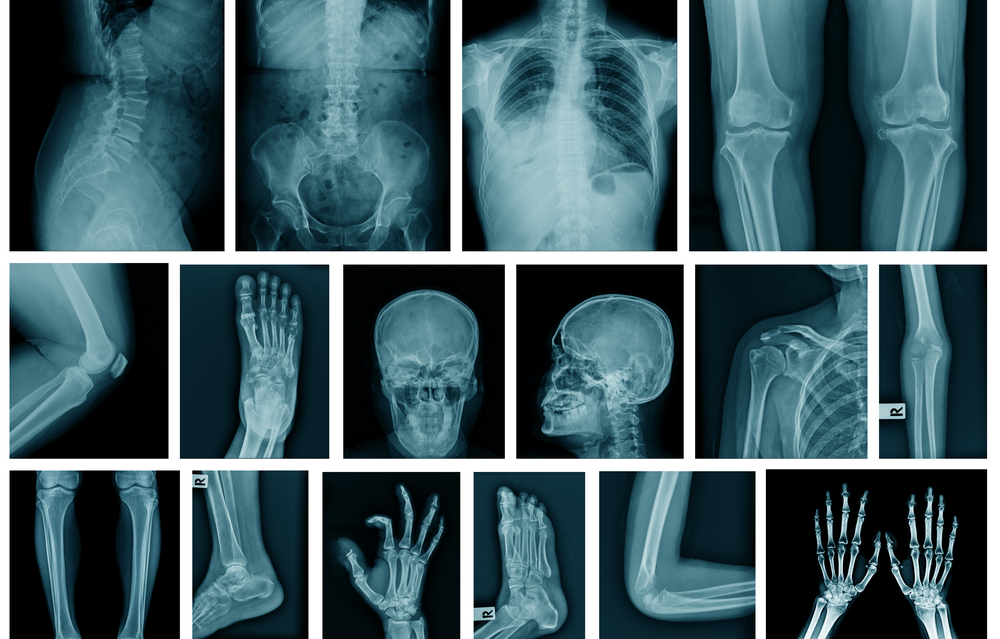

미국, 캐나다, 호주, 대만의 과학자가 포함된 연구팀은 먼저 X선 및 CT 스캔의 표준 데이터 세트를 사용하여 AI 시스템을 훈련했으며 각 이미지에는 개인의 인종이 표시되었다. 이미지는 가슴, 손, 척추를 포함한 신체의 다른 부분에서 가져왔다. 컴퓨터로 검사한 진단 이미지에는 피부색이나 머리카락 질감과 같은 명백한 인종 표시는 포함되지 않았다.